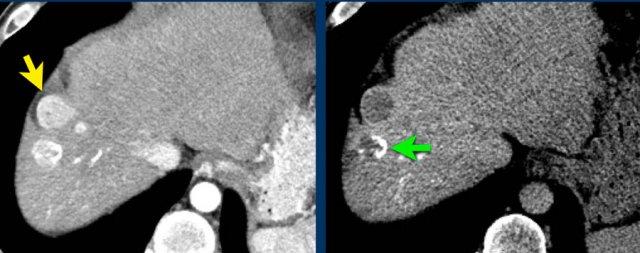

TRÁI: Tổn thương tăng ngấm thuốc phát hiện tại phân thùy 5. PHẢI: Theo dõi sau 3 tháng cho thấy tổn thương tăng kích thước.

Kích thước – Tăng trưởng vượt ngưỡng

Kích thước cũng là yếu tố quyết định tổn thương được xếp vào phân loại nào.

Tổn thương càng lớn, khả năng là HCC càng cao.

Tổn thương cần được đo trong thì, chuỗi xung hoặc mặt phẳng mà bờ tổn thương hiện rõ nhất.

Nên tránh đo kích thước trên thì động mạch và chuỗi xung DWI vì kích thước có thể bị ước tính quá mức do hiện tượng tổng hợp ngấm thuốc quanh tổn thương và biến dạng giải phẫu tương ứng.

Tăng trưởng vượt ngưỡng cũng là một dấu hiệu quan trọng.

Được định nghĩa là tăng kích thước hơn 50% trong vòng dưới 6 tháng.

Các hình ảnh cho thấy một tổn thương tại phân thùy 5 của gan có biểu hiện tăng ngấm thuốc thì động mạch.

Tổn thương đã tăng kích thước từ 8 mm lên 21 mm trong 3 tháng, đáp ứng tiêu chí tăng trưởng vượt ngưỡng.